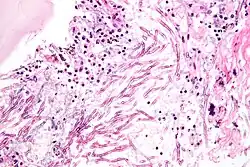

Some Aspergillus species cause serious disease in humans and animals. The most common pathogenic species are A. fumigatus and A. flavus, which produces aflatoxin which is both a toxin and a carcinogen, and which can contaminate foods such as nuts. The most common species causing allergic disease are A. fumigatus and A. clavatus. Other species are important as agricultural pathogens. Aspergillus spp. cause disease on many grain crops, especially maize, and some variants synthesize mycotoxins, including aflatoxin. Aspergillus can cause neonatal infections.[39]

A. fumigatus (the most common species) infections are primary pulmonary infections and can potentially become a rapidly necrotizing pneumonia with a potential to disseminate. The organism can be differentiated from other common mold infections based on the fact that it takes on a mold form both in the environment and in the host (unlike Candida albicans which is a dimorphic mold in the environment and a yeast in the body).

Aspergillosis

Aspergillosis is the group of diseases caused by Aspergillus. The most common species among paranasal sinus infections associated with aspergillosis is A. fumigatus.[40] The symptoms include fever, cough, chest pain, or breathlessness, which also occur in many other illnesses, so diagnosis can be difficult. Usually, only patients with already weakened immune systems or who suffer other lung conditions are susceptible.

In humans, the major forms of disease are:[41][42]

- Acute invasive aspergillosis, a form that grows into surrounding tissue, more common in those with weakened immune systems such as AIDS or chemotherapy patients

- Allergic bronchopulmonary aspergillosis, which affects patients with respiratory diseases such as asthma, cystic fibrosis, and sinusitis

- Aspergilloma, a "fungus ball" that can form within cavities such as the lung

- Disseminated invasive aspergillosis, an infection spread widely through the body